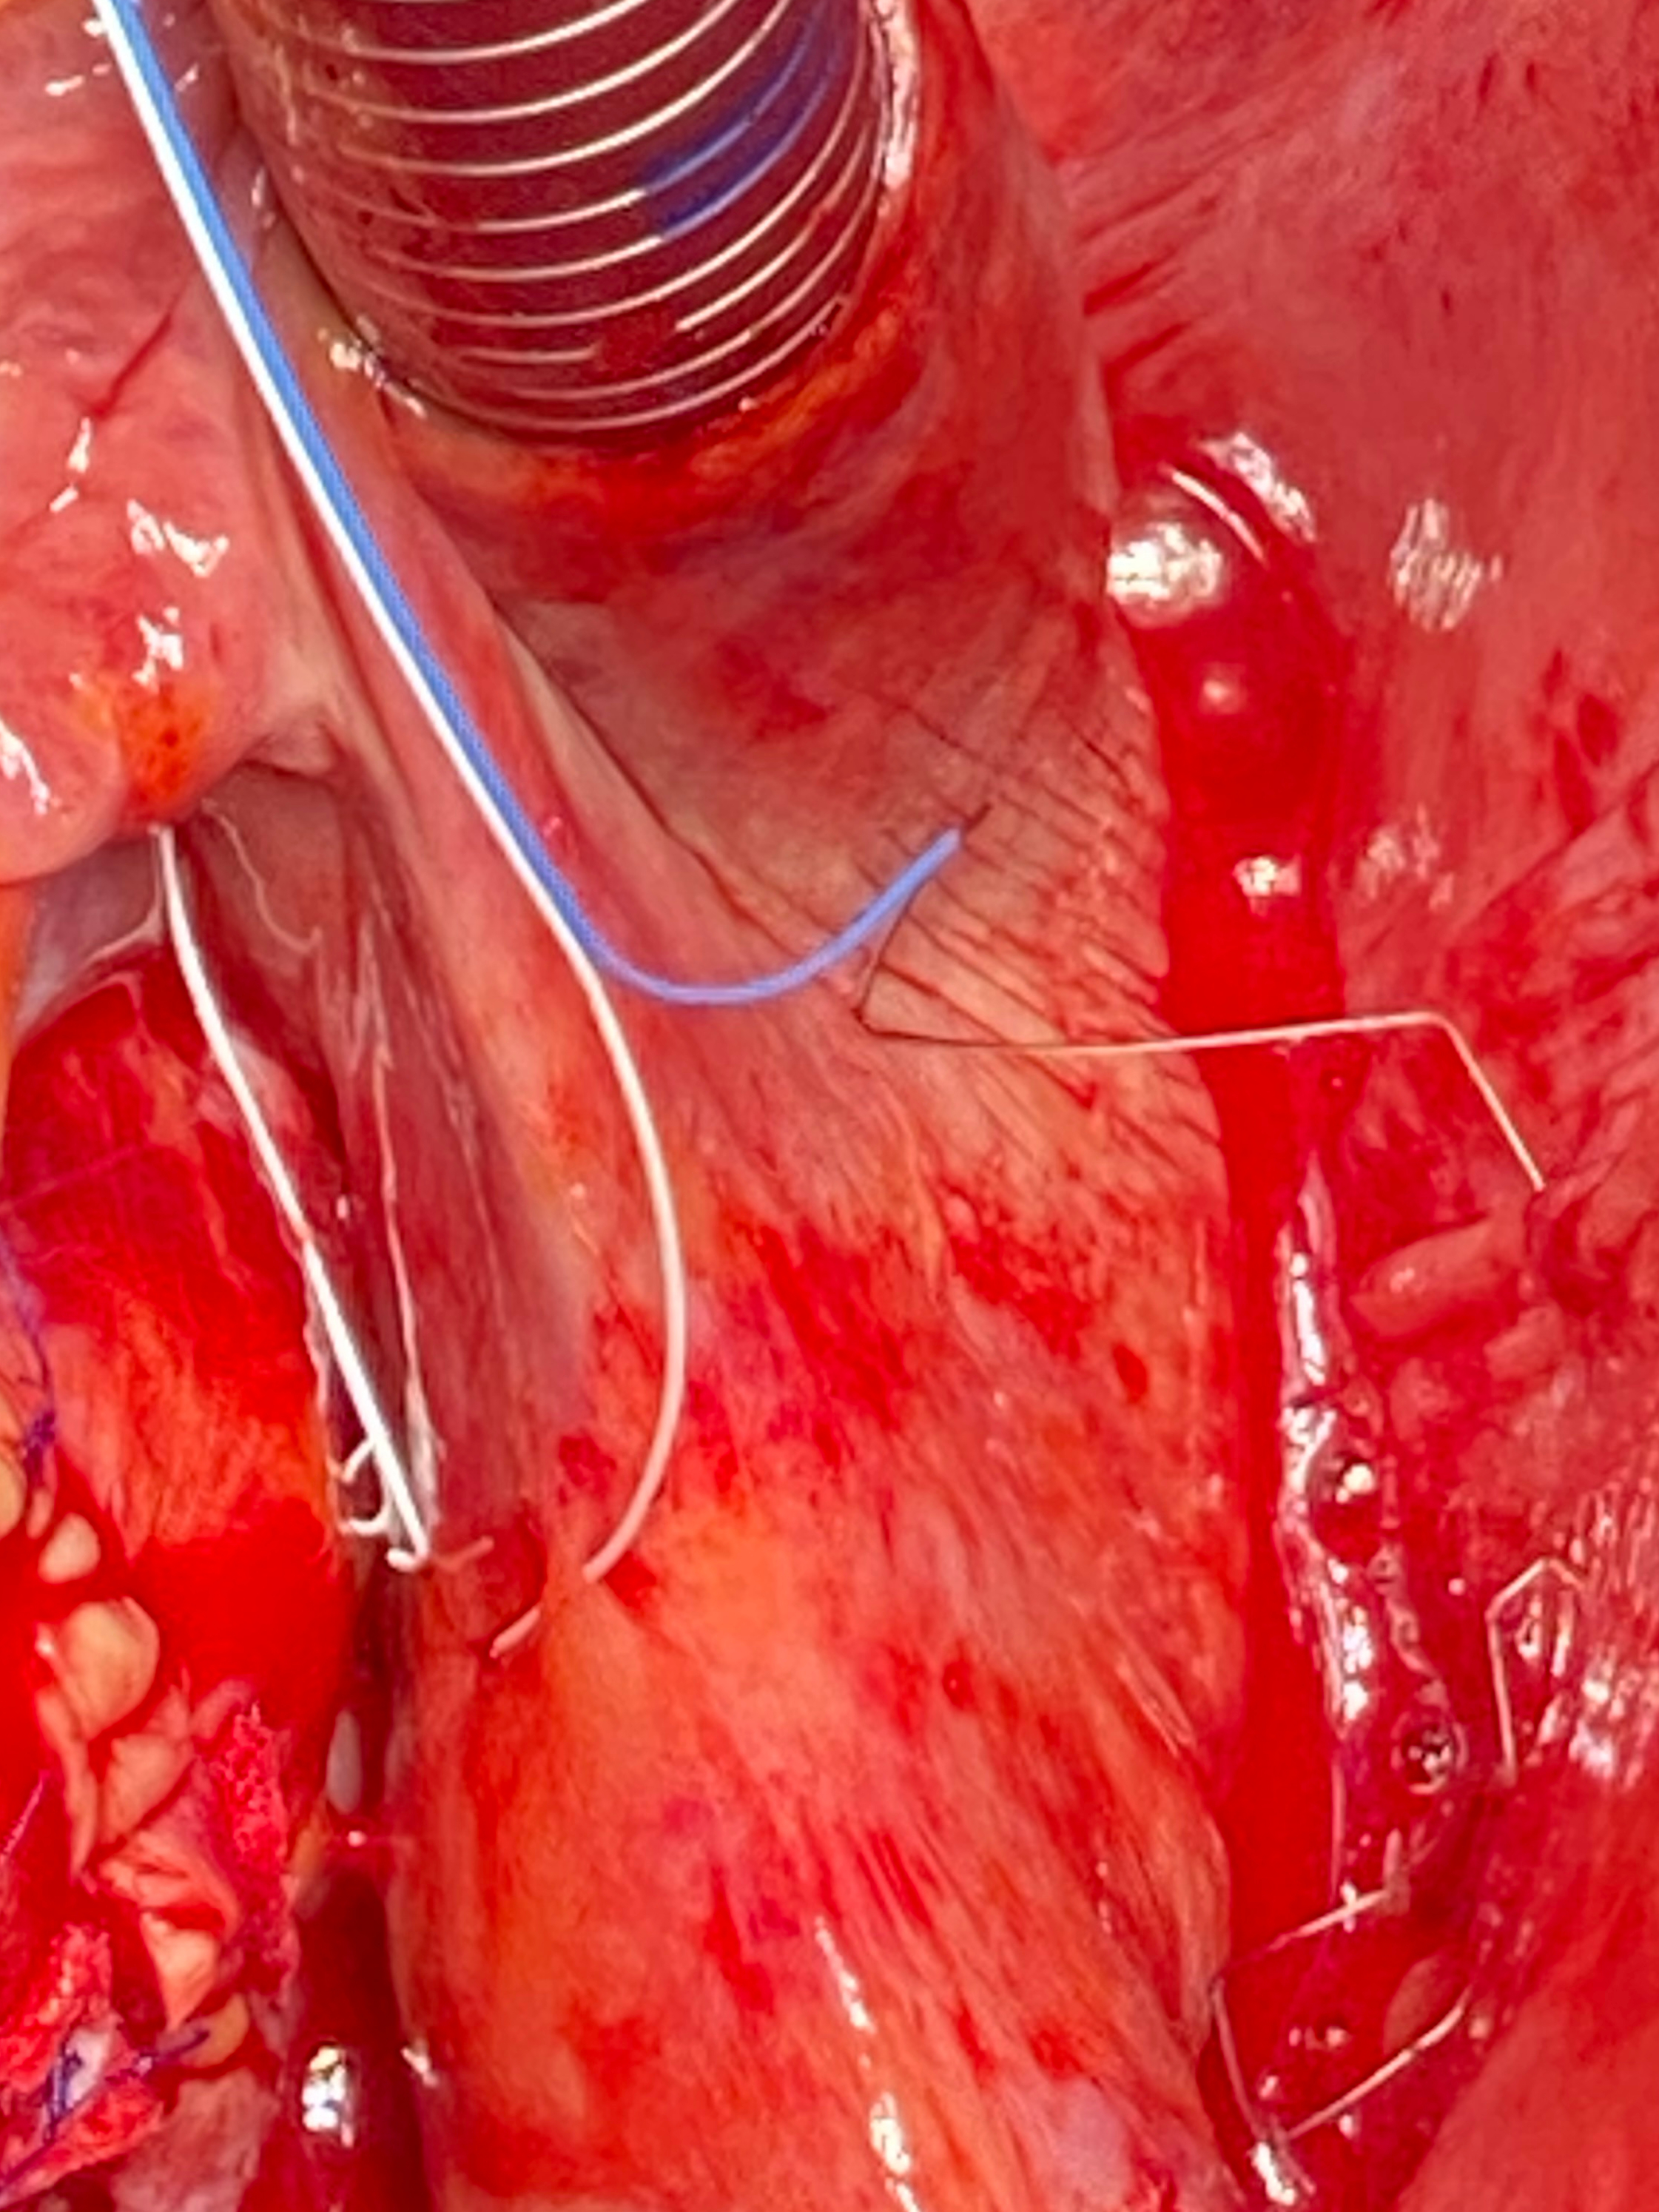

The temporary left atrial electrodes were either transferred through the

transverse sinus for placement at the left atrium without fixation (Figs. 2b, 3)

or fixated on the epicardial or pericardial surface based on the preference of

the individual surgeon. In case the electrodes were fixed, the anode

(defibrillation zigzag) was either placed and fixed between the free wall of the

left atrial appendage or fixed to the pericardium and the left upper pulmonary

vein (Fig. 2b). The cathode was placed one to two cm distal from the anode. The

Fig. 3.Implantation of the atrial TMA® electrodes without needle: placement of the TMA® wire transferred through the transvers sinus for placement at the left atrium without fixation.